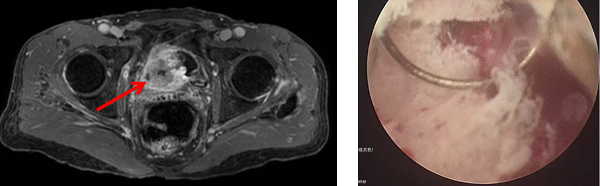

在顺利完成3个周期的规范联合治疗后,2026年1月,复查的影像学检查显示,张先生原膀胱内的巨大肿块已经基本消失,受侵犯的输尿管管壁及周围组织也得到修复,右肾积水明显减轻。

3.手术再评估。为了进一步治疗评估,团队对张先生原肿瘤部位及周围组织进行了充分切除。病理结果显示已无癌细胞残留。这意味着,综合治疗让张先生体内的肿瘤得到清除的同时,膀胱功能也完整地保留了下来。经泌尿肿瘤MDT团队讨论,下一步还将继续实施化疗免疫“善后”,巩固治疗成果。

术后影像显示肿瘤被切除